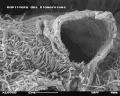

Scanning electron microscope view of the inner surface of an opened (broken) capillary with fenestrae visible (100,000x magnification)

Capillaries of the glomerulus are lined by endothelial cells. These contain numerous pores—also called fenestrae—, 50–100 nm in diameter.[4] Unlike those of other capillaries with fenestrations, these fenestrations are not spanned by diaphragms.[4] They allow for the filtration of fluid, blood plasma solutes and protein, while at the same time preventing the filtration of red blood cells, white blood cells, and platelets.